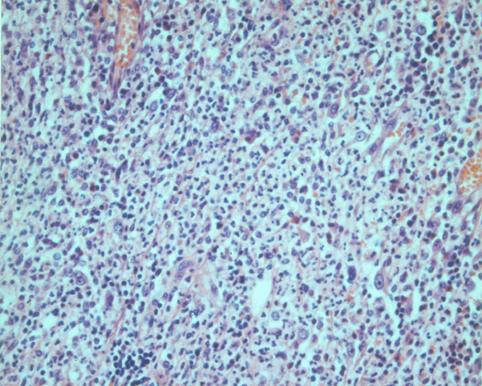

A case of phlegmonous appendicitis with stone.

Inflammatory or ulcerative disease / lesions/Others

Large intestine(Colon)/Appendix

Histology